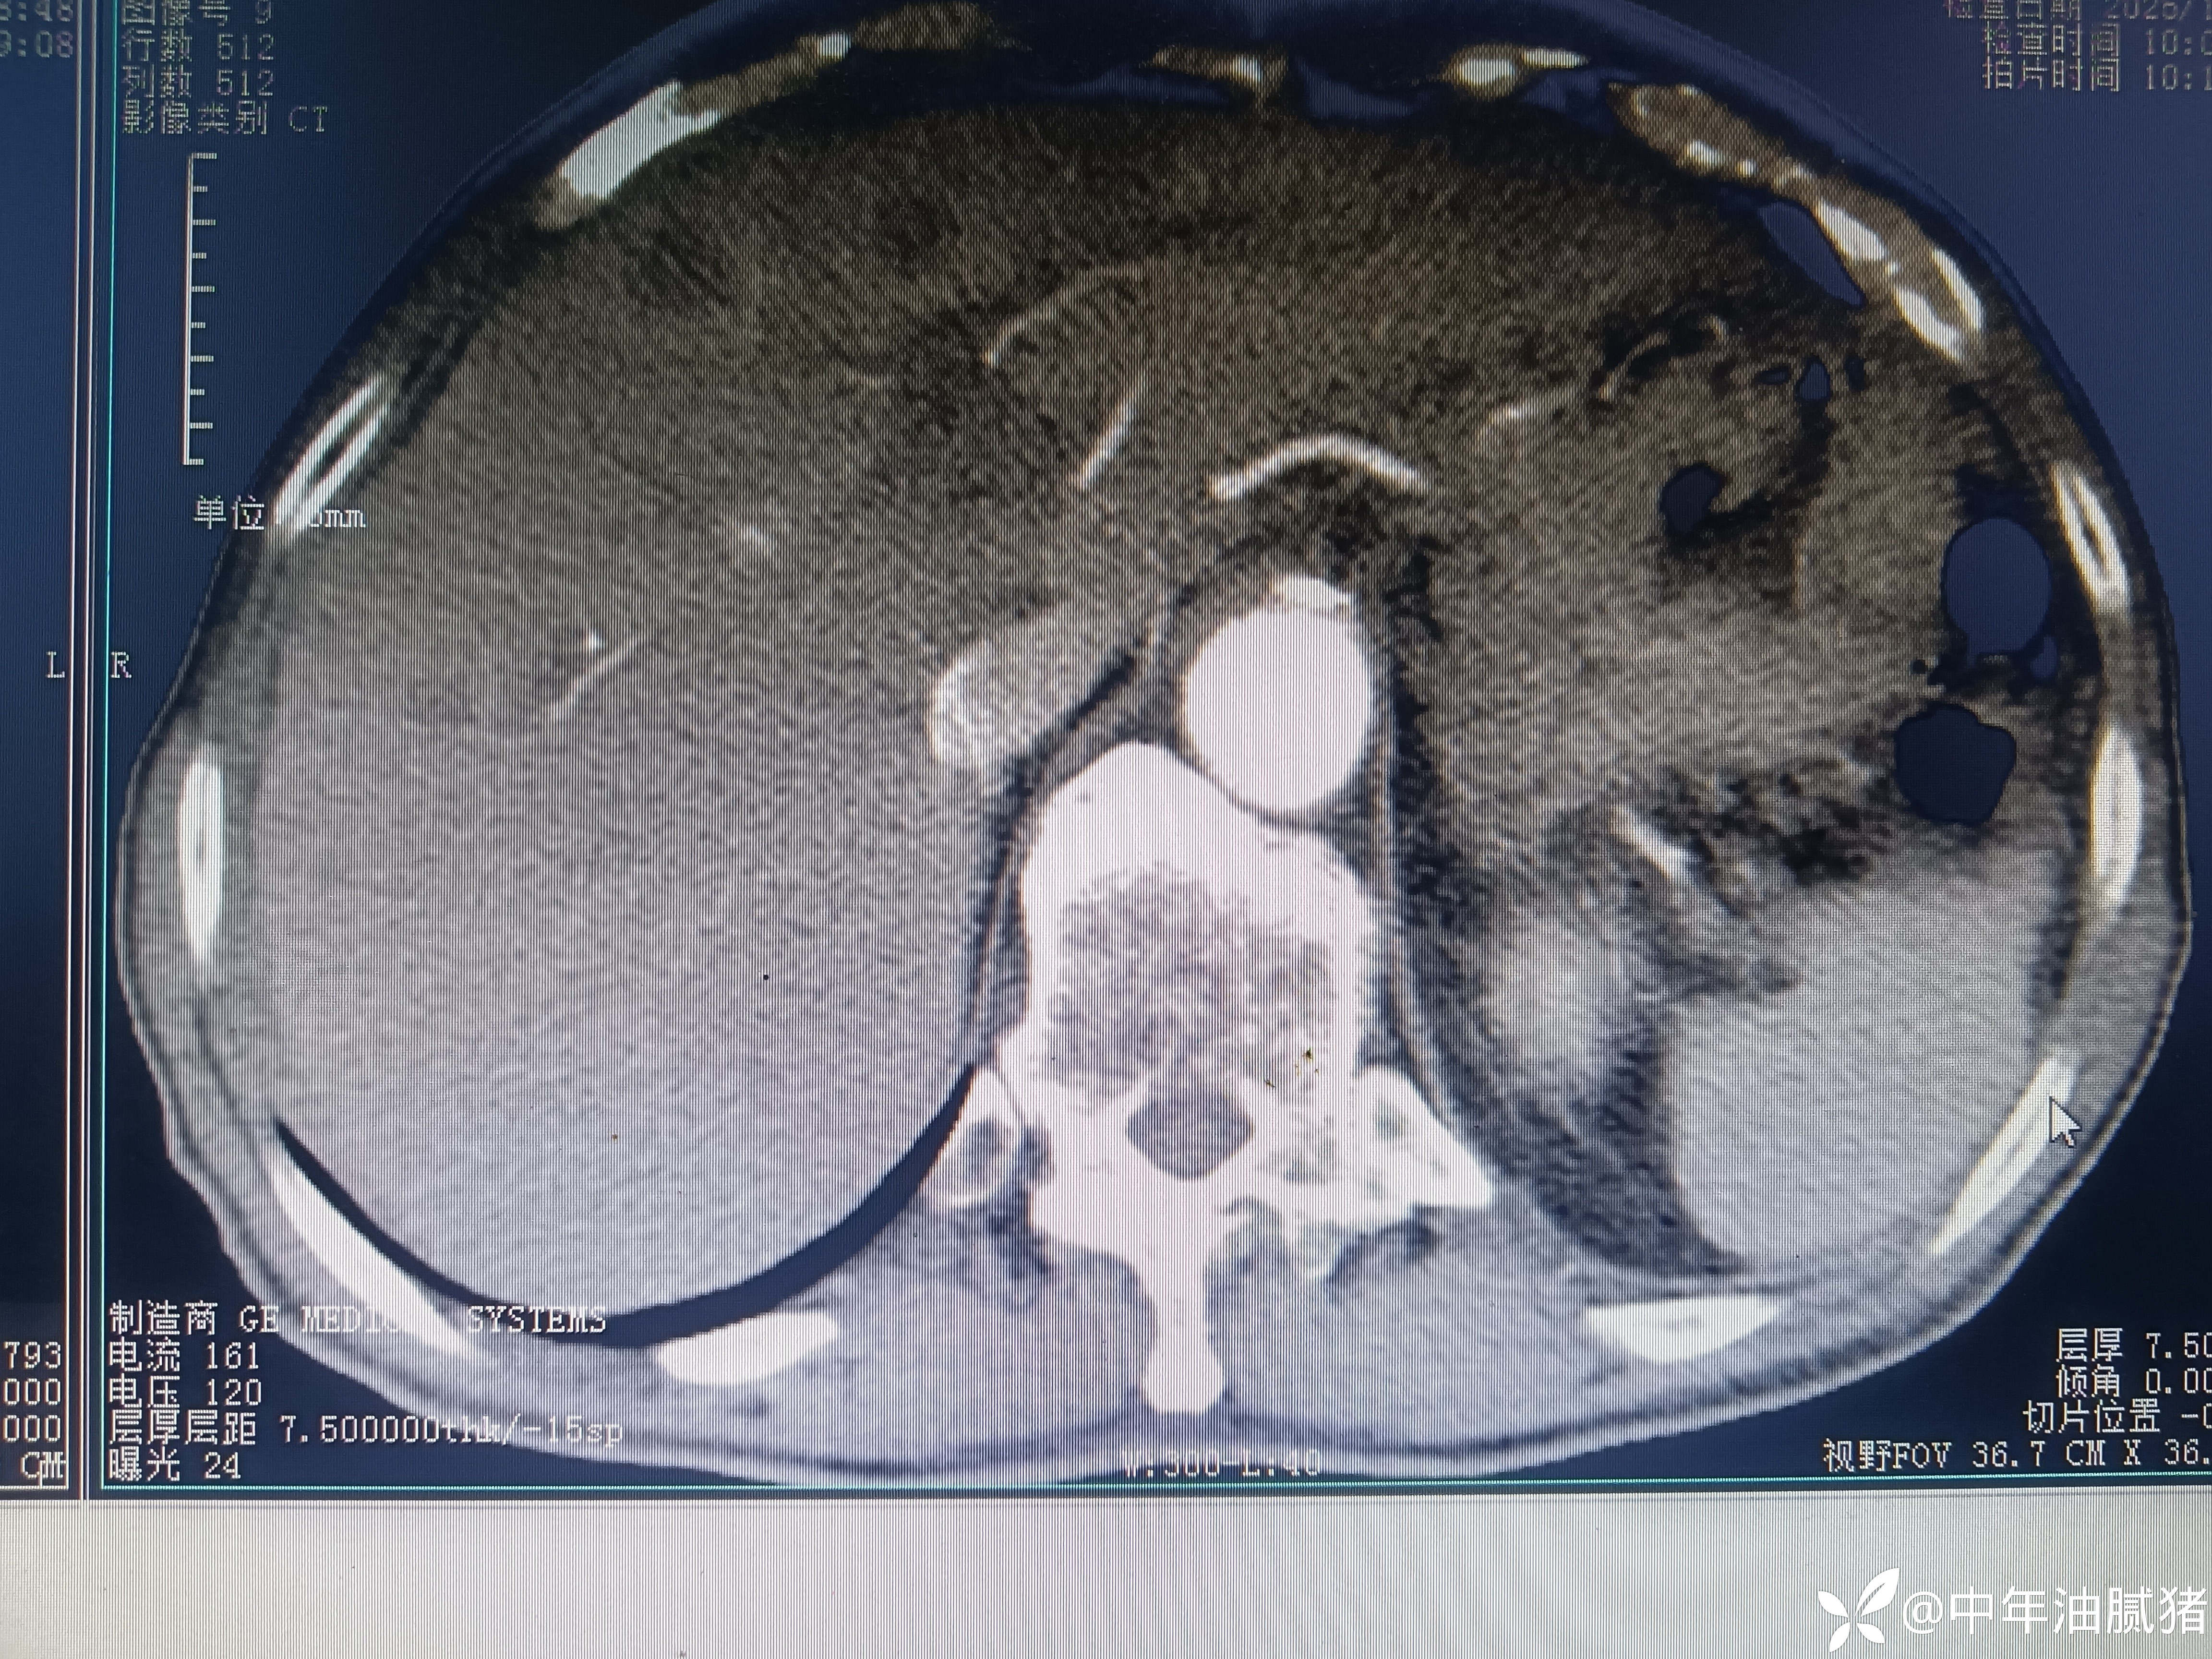

肺ct看到肝内病灶,行增强检查

男,72岁,感胸痛7天,不剧,咳嗽时略明显,有吸烟,行肺ct报告如下

建议增强ct.报告如下

考虑肝囊肿?让他走?

我腹部ct不在行,但我记的有位大家说过:一流的先看影像再看报告,二流的先看报告再看影像,三流的只看报告!我生性浪荡,让人不安,属于二流子!上图

看后,我隐隐约约觉的不是肝囊肿那么简单?元芳,你怎么看?狄阁老,我也是这么认为!摇人,掏起手机:喂,w主任,请帮我看看这个ct。5分钟后报告修改如下